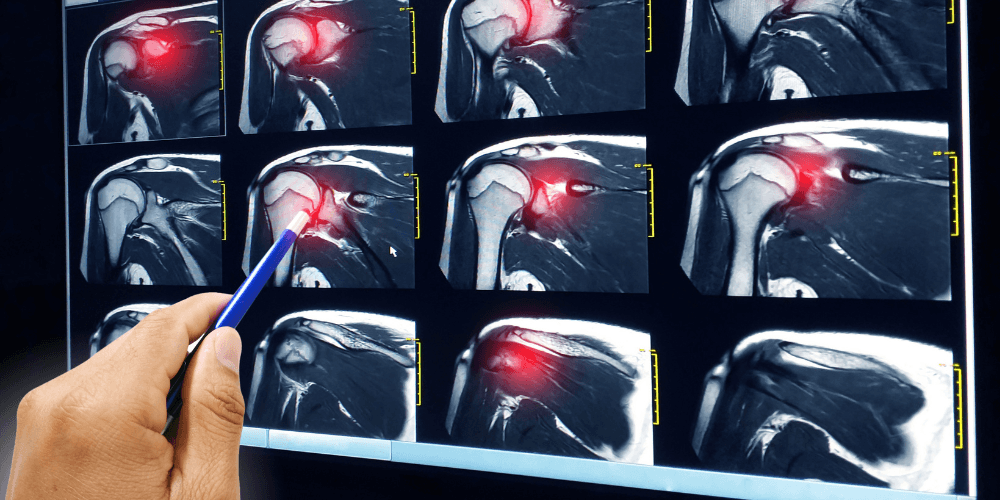

Imaging tests, such as X-rays or magnetic resonance imaging (MRI), may be used to confirm the diagnosis. An MRI can show the rotator cuff tear, as well as where the tear is located within the tendon and the size of the tear.